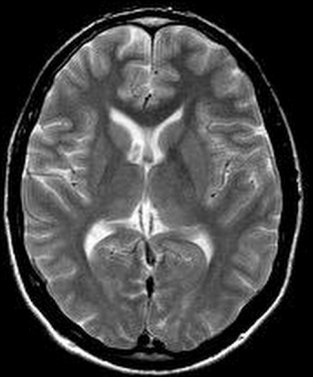

T2 weighted (T2W) image: TR and TE are long. (TR = 2000 ms, TE = 80 ms). Characteristic signal intensities: fat is mild, water is very intense, the signal intensity of other tissues is determined by their water content, flowing blood is still signal free.

- T1W image: (brain, sagitta slice, arachnid cyst)